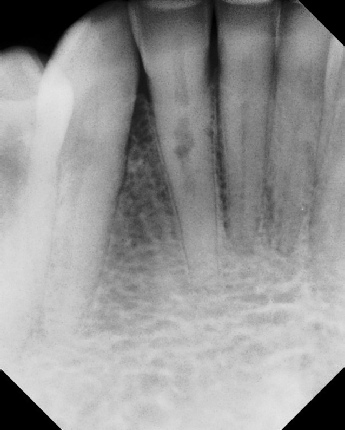

COMPLICATED ANATOMY LARGE LESIONS CALCIFIED CANALS PERFORATION / RESORPTION SEPARATED INSTRUMENTS SURGICAL CASES RETREATMENT / pOST REMOVAL OPEN APICES ACCESS THRU CROWNS Root Canal Case Portfolio